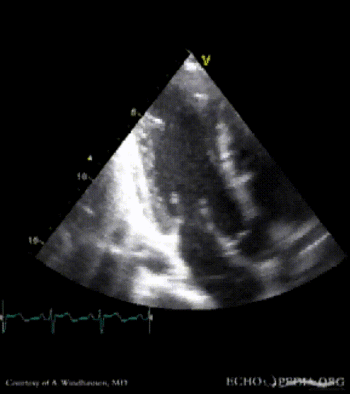

Severe Hypertrophic Cardiomyopathy (HCM)

Case description: Severe Hypertrophic Cardiomyopathy (HCM)

Courtesy of: A. Windhausen, AMC, The Netherlands